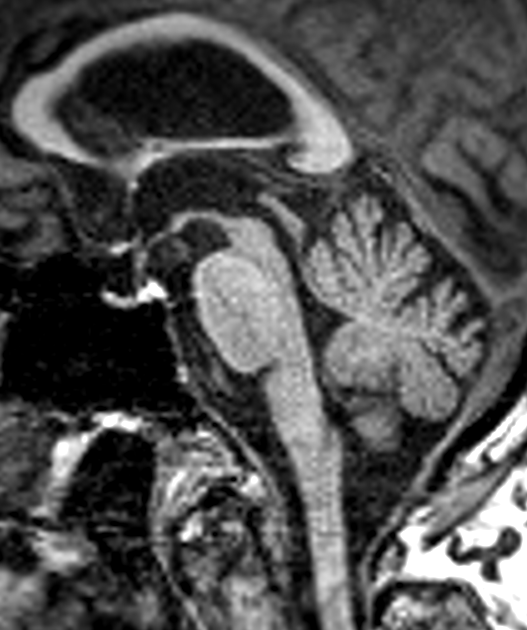

- Imaging shows midbrain atrophy with the 'hummingbird' sign in the sagittal plane

- Imaging shows excessive midbrain volume loss

Imaging